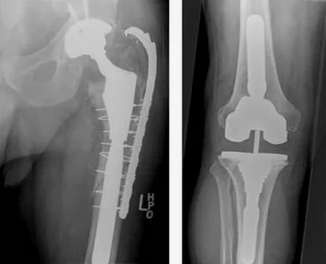

В случае перелома шейки бедра компания МосРентген Центр госпитализирует в Склиф для эндопротезирования.